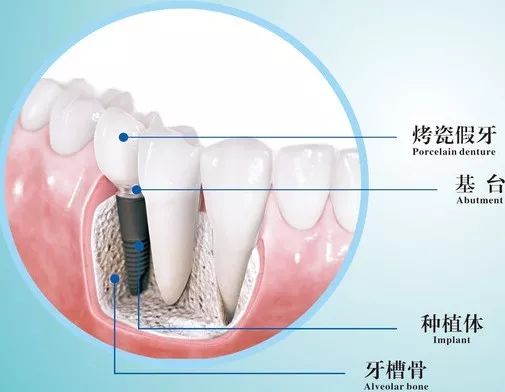

种植牙(Implant)就是将纯钛的人工牙根植入患者的颌骨内,以骨整合(Osseointegration)的方式与颌骨融合在一起,通过基台(Abutment)与上部的假牙(Crown)连接在一起而行使功能。